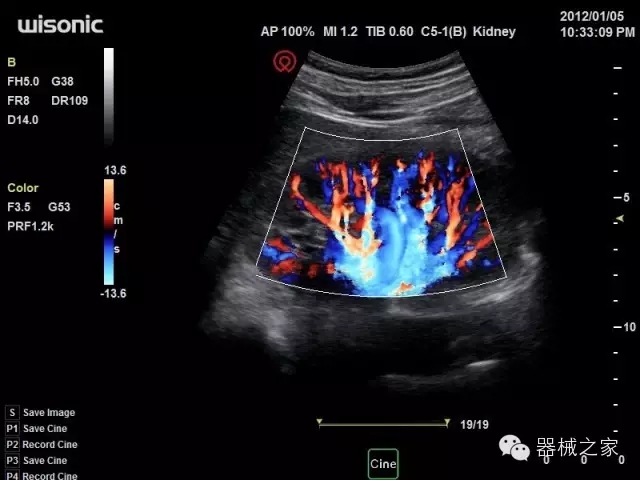

經(jīng)典產(chǎn)品:四葉草

臨床圖片賞析

·全球目前唯一一款配備主機(jī)雙探頭接口,整機(jī)重量(含電池)在5公斤以內(nèi)的便攜式彩超;

·獨(dú)有的HoloTM PW 實(shí)時(shí)3取樣門PW成像技術(shù),精確進(jìn)行血管診斷;

·一鍵優(yōu)化B、Color、PW,Auto Doppler自動(dòng)識(shí)別血管位置、偏轉(zhuǎn)角度等,提高工作效率;